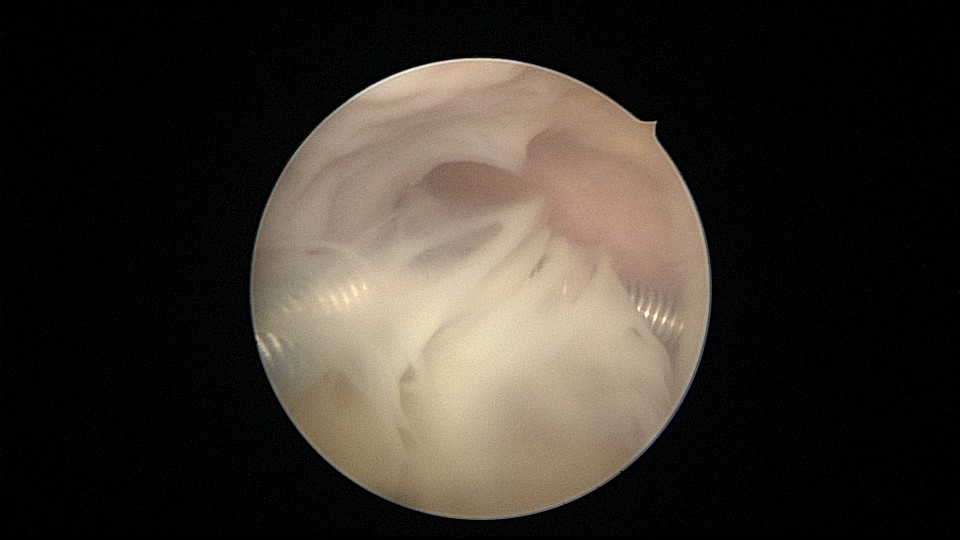

患者55岁,G5P1,顺产1次。安环20年,绝经8年。子宫后位,外阴、阴道及宫颈萎缩,宫深6.5cm,宫颈内口封闭粘连,镜鞘推开粘连,见灰白色脓液,O型环位置正常,异物钳顺利取出节育环,膨宫液冲洗脓液,宫腔无其他异常。